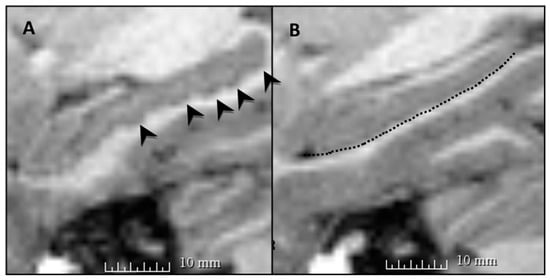

Figure 3. Both (A,B) show sagittal views of left hippocampi from two different 18-year-old participants. (A) A hippocampus with multiple dentes (indicated by black arrowheads), and (B) a relatively flat hippocampus, with the inferior surface traced by the black dotted line. This highlights the variability in hippocampal dentation observed among healthy individuals of the same age. Hippocampal dentation is pictured here in a single representative sagittal slice for each participant.

4.2. Variability of Hippocampal Dentation by Age

While primary analyses revealed a significant positive association between age and number of hippocampal dentes, visual inspection of the data (see Figure 4) indicated that while younger children tend to have fewer hippocampal dentes, older children and adolescents display wide variability in the number of hippocampal dentes. This was supported by a post-hoc analysis, which revealed a positive association between age group and variability in hippocampal dentation (i.e., standard deviation). The observed degree of variability found in our current study is consistent with a previous finding in a healthy adult cohort, where a wide range of hippocampal dentation was observed []. In a study examining volume, substantial variability in hippocampal volume was observed in healthy children aged 4–18 years old; however, the results did not indicate whether the distribution of hippocampal volume varied with age [].